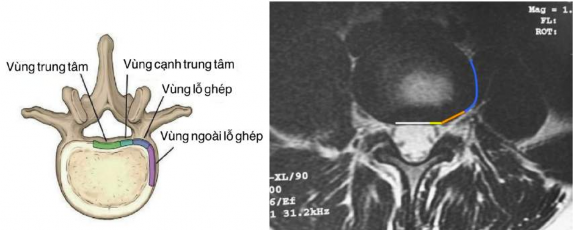

+ Hình ảnh T1 hoặc T2 cắt ngang phát hiện được:

. Thoát vị đĩa đệm ra sau (thể trung tâm, trung tâm lệch bên trái hoặc bên phải, vào lỗ ghép) (Hình 2.3).

Hình 2.3. Hình ảnh cách xác định thoát vị đĩa đệm liên quan đến rễ thần kinh [45].

. Mức độ chèn ép bao rễ, rễ thần kinh và ống sống của thoát vị đĩa đệm ra sau.